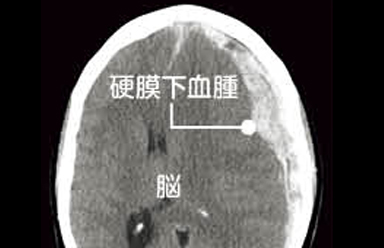

CT画像で見る硬膜下血腫

頭部打撲後に頭痛や歩行困難で受診された患者様の頭部CT画像です。脳の表面に三日月型のスペースがみられ脳(灰色)は中心部に圧迫され変形を伴っています。この脳の変形が手足の麻痺症状に関係しています。